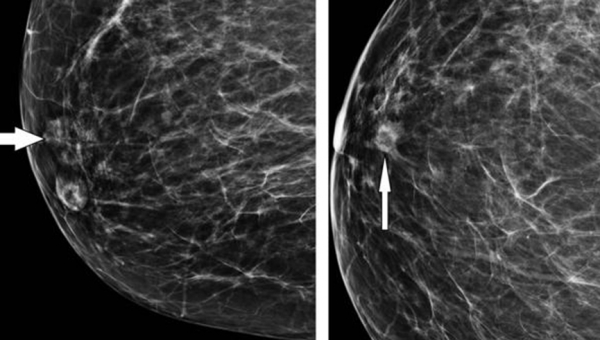

Aunque no se conoce el nivel de incidencia, el embarazo ectópico en cicatriz de cesárea previa puede ocurrir y se presenta como todo un reto para el personal médico especialista que trata el caso.

Es considerada una forma novedosa y potencialmente mortal de implantación anormal de un saco gestacional dentro del miometrio y el tejido fibroso de la cicatriz.